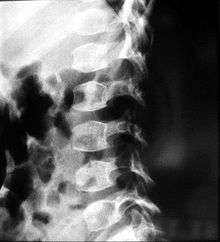

| A 6 1⁄2-year-old male with spondyloepiphyseal dysplasia congenita. Short stature, disproportionately short trunk, and kyphoscoliosis. | |

People with spondyloepiphyseal dysplasia are short-statured from birth, with a very short trunk and neck and shortened limbs. Their hands and feet, however, are usually average-sized. This type of dwarfism is characterized by a normal spinal column length relative to the femur bone. Adult height ranges from 0.9 meters (35 inches) to just over 1.4 meters (55 inches). Curvature of the spine (kyphoscoliosis and lordosis) progresses during childhood and can cause problems with breathing. Changes in the spinal bones (vertebrae) in the neck may also increase the risk of spinal cord damage. Other skeletal signs include flattened vertebrae (platyspondyly), a hip joint deformity in which the upper leg bones turn inward (coxa vara), and an inward- and downward-turning foot (called clubfoot). Decreased joint mobility and arthritis often develop early in life. Medical texts often state a mild and variable change to facial features, including cheekbones close to the nose appearing flattened, although this appears to be unfounded. Some infants are born with an opening in the roof of the mouth, which is called a cleft palate. Severe nearsightedness (high myopia) is sometimes present, as are other eye problems that can affect vision such as detached retinas. About one-quarter of people with this condition have mild to moderate hearing loss.